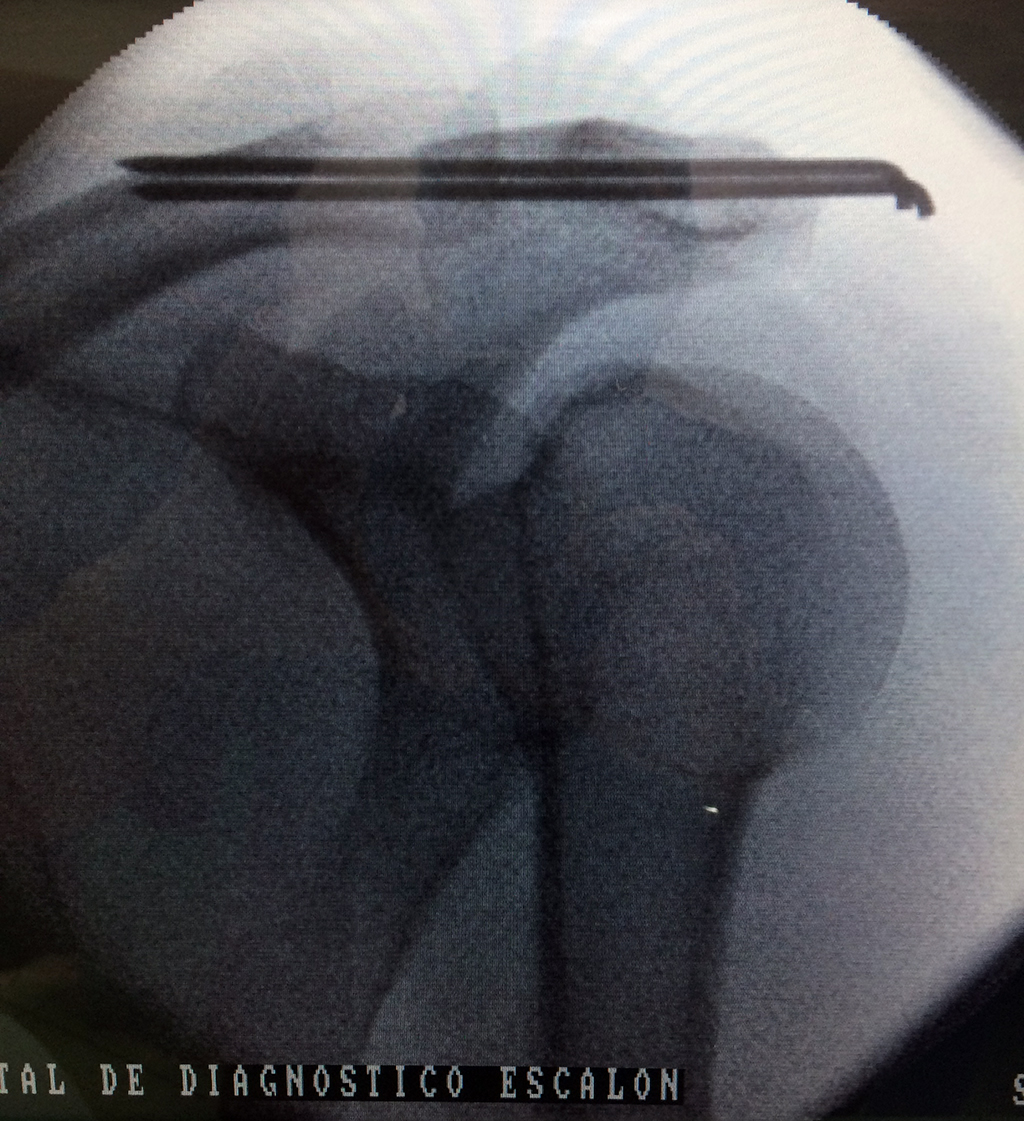

La clavícula es un hueso largo, con forma de "S" itálica, situado en la parte anterosuperior del tórax. Junto con la escápula forman la cintura escapular. Se puede palpar por toda su longitud y se extiende del esternón al acromion de la escápula, siguiendo una dirección oblicua lateral y posterior.